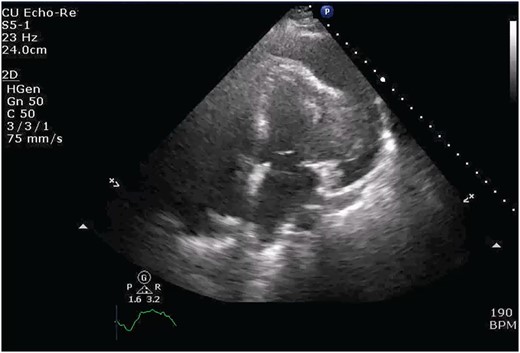

Cardiothoracic surgery team was consulted, and the patient underwent a pericardial window with 750 cc of serosanguinous fluid drained from her pericardial space. A chest tube placed status-post pericardial window, which initially continued to drain 500 cc of serosanguinous fluid, with fluid volume decreasing in the following 5 days with stable vital signs. The patient tolerated the switch to p.o. amiodarone and discharged upon her request to restart chemotherapy, after removal of her chest tube. Histopathology results of the pericardial fluid were positive for reactive mesothelial cells and chronic inflammation. Follow-up positron emission tomography (PET)/CT scan depicted increased uptake in the cardiac chamber (Fig. 4). Repeated echocardiography 2 months later depicted a return in pericardial fluid with the patient remaining hemodynamically stable with preserved ejection fraction.